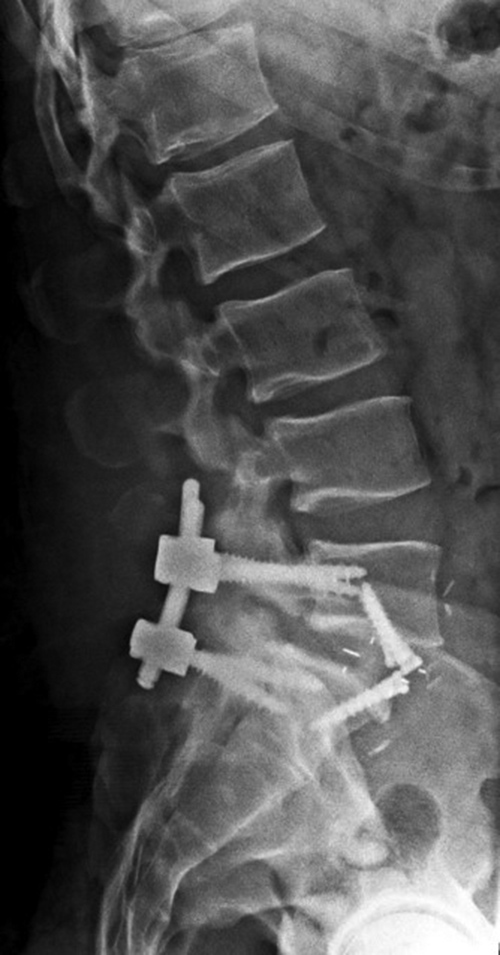

Lumbar spine bony disk strut, pedicle screws, and pedicle rods (lateral view) |

20 year-old woman with L1 vertebral body compression fracture treated with T12-L2 posterior spinal fusion using pedicle screws at T12 and L2 with connecting rods on each side. |

| Screws are placed through the pedicles into the vertebral bodies. The screws are connected together on each side with rods or a plate placed over the pedicle screws on each side. Some of these systems are also combined with posterolateral bony fusion masses. |